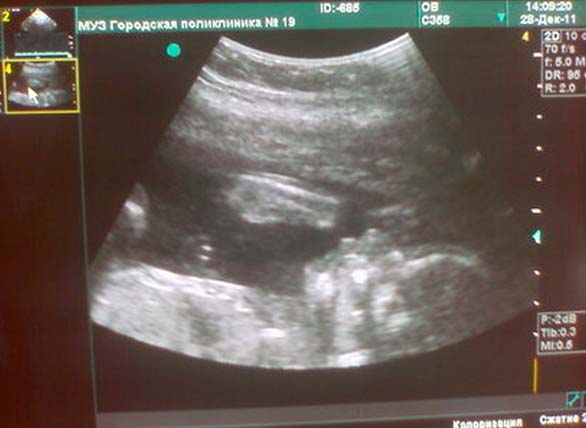

Si vous n'avez pas subi d'échographie, le médecin vous prescrira probablement une référence. Au cours de l'étude, le médecin vérifiera les paramètres physiques du fœtus, vérifiera avec les indicateurs normatifs de la quantité de liquide amniotique, vérifiera l'état du placenta.

Photo échographique à la semaine 22